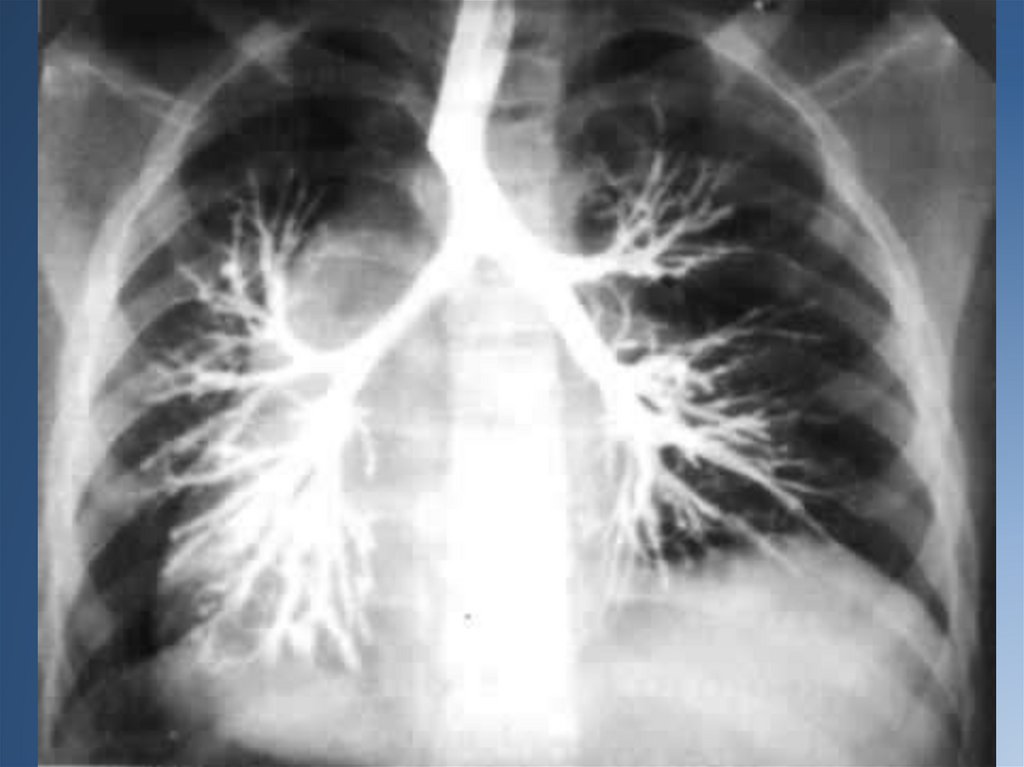

При стихании процесса проводят контрастную бронхографию для выявления характера и

локализации бронхоэктазов с целью последующего возможного оперативного их

удаления.